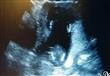

شاهد جنين يصفق ويرقص داخل رحم امه